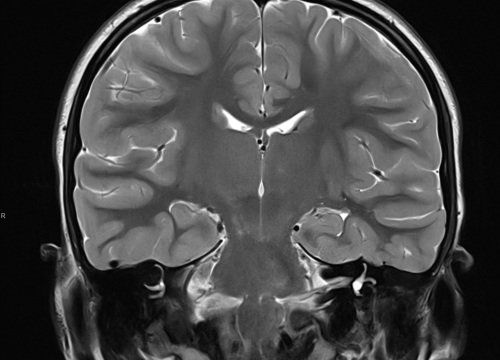

FOTO Ako su vam potrebni specijalistički pregledi mamografija, RTG, UZV, CT i MR, koji se inače koriste za dijagnostiku velikog broja zdravstvenih problema, možete ih obaviti već danas ili sutra. Vodite računa o vašem zdravlju i zakažite pregled u Poliklinici Affidea Vita u Šibeniku na vrijeme!